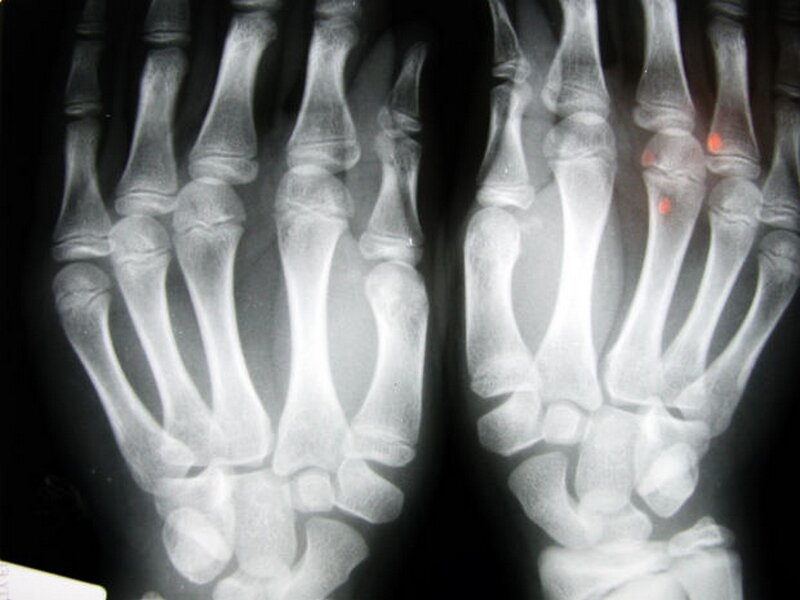

Как выглядит перелом на рентгене?

В случае большого ушиба на снимке будет визуализировано небольшое затемнение с неровными контурами, а при переломе видны смещения осколков кости.